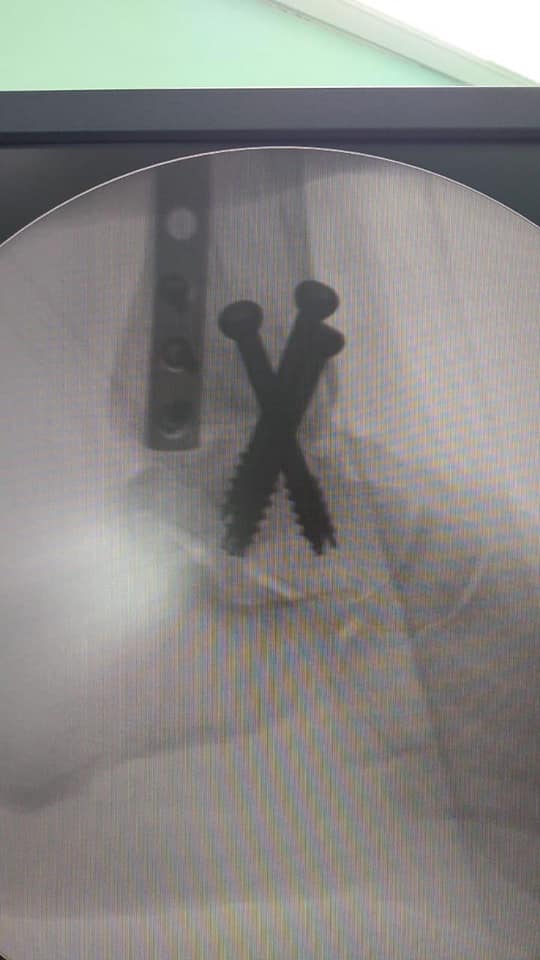

Essas são imagens de antes e depois feitas via Raio X onde foi realizado uma Artrodese de Tornozelo pelo

Doutor Luciano Moraes Brasil, Especialista em Pé e Tornozelo